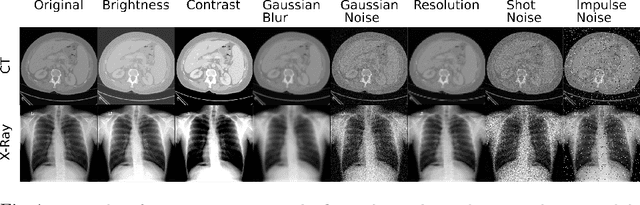

Abstract:Self-supervision has demonstrated to be an effective learning strategy when training target tasks on small annotated data-sets. While current research focuses on creating novel pretext tasks to learn meaningful and reusable representations for the target task, these efforts obtain marginal performance gains compared to fully-supervised learning. Meanwhile, little attention has been given to study the robustness of networks trained in a self-supervised manner. In this work, we demonstrate that networks trained via self-supervised learning have superior robustness and generalizability compared to fully-supervised learning in the context of medical imaging. Our experiments on pneumonia detection in X-rays and multi-organ segmentation in CT yield consistent results exposing the hidden benefits of self-supervision for learning robust feature representations.